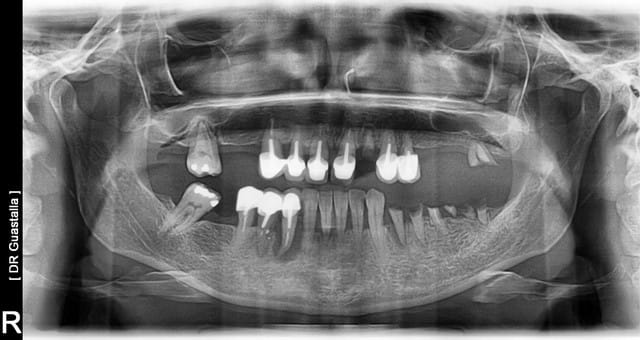

Essayons un Exercice pratique:

Patiente 35 ans, se présente en consultation, elle raconte qu'elle n'ose plus sourire, elle a fait faire des couronnes devant en haut, mais il y a 2 mm de racine visible, et seules 23 et 16 ne sont pas mobile au maxillaire....

Comment gérez vous la consultation et la suite.

Je vous mettrais ma chronologie détaillée par la suite.....

Après la pano, et l'examen clinique, je lui parlerais de sa maladie des gencives, que cette maladie est dans une forme très grave.

Si je le sens, je lui dirais que malheureusement ses dents ne sont pas sauvables.

En général, surtout à cet âge là, la patiente ne s'y attend pas et souvent les larmes viennent. Et à partir de ce moment là je ne sais plus gérer, en général elle se ferme.

Si au contraire elle s'en doutait et vient pour la solution, là je n'ai aucun mal à lui parler d'extraction totale, pose de deux appareils provisoires le jour des extractions, et réalisation de deux PAC, avec complément de rétention implantaire à la mandibule. Je propose également la solution fixe sur implant, mais en général c'est refusé (j'ai un seul patient qui a accepté avant de décéder avant la pose, malheureusement véridique).